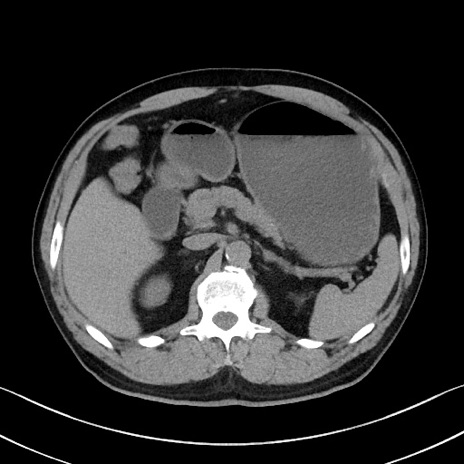

症例35(横断像)

冠状断像

【症例】70歳代 男性

【主訴】腹部膨満、嘔吐

【現病歴】昨日より腹部膨満感出現。本日増悪し、仙痛出現。嘔吐あり、受診。

【既往歴】糖尿病、胆摘後

【身体所見】BP 149/80mmHg、HR 74/min、BT 35.9℃、腹部:膨満、軟、圧痛なし。腸雑音減弱あり。上腹部正中切開瘢痕あり。

【データ】WBC 13500、CRP 1.72